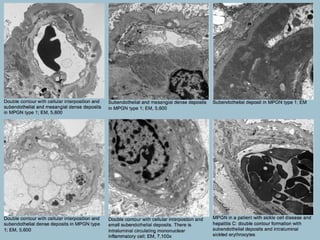

• Electron microscopy:

• Visceral epithelial cells: Focal, sometimes marked effacement of

visceral epithelial cell foot processes

• Glomerular basement membranes: Prominent subendothelial

widening due to cellular interposition and electron-dense deposits;

secondary basement membrane forms under the displaced

endothelium (double contour formation)

• Glomerular endothelial cells: Show loss of fenestrations and other

non-specific changes; they do not contain tubuloreticular structures

• Mesangium: Mesangial expansion due to increased number of

mononuclear inflammatory cells, an increase in the amount of

matrix and a presence of electron-dense deposits

(MPGN), type III (Burkholder, and

Strife and Anders variants)

• Type III membranoproliferative

glomerulonephritis (MPGN) consists of two

variants; Burkholder variant (MPGN type I

with subepithelial deposits) and Strife and

Anders variant (complex intramembranous

and subendothelial deposits, with marked

basement membrane irregularities). Electron

microscopy is essential in distinguishing these

variants from classic type I MPGN.

• Glomerular basement membranes: In the Burkholder variant, in

addition to subendothelial deposits similar to MPGN type I, there

are subepithelial, sometimes “hump”-like electron-dense deposits.

In the Strife and Anders variant, there are complex

intramembranous and subendothelial deposits, with marked

basement membrane irregularities; there is breakage, lamellation,

and disrupted appearance of the basement membranes

matrix, and a presence of electron-dense deposits